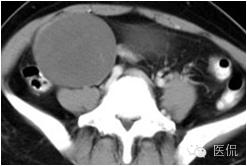

卵巢卵泡膜细胞瘤

卵泡膜细胞瘤也是来源于性索间质的肿瘤,较为少见。多数肿瘤分泌雌激素,青春期前可出现性早熟,绝经前可出现月经紊乱,引起子宫内膜增厚。CT 表现为均质软组织实性密度肿物,少数可有部分囊变、出血、坏死或钙化,肿物边缘清楚,临床如无内分泌异常表现,术前定位定性均较为困难。卵巢纤维瘤与卵泡膜细胞瘤是同一起源的肿瘤,但纤维瘤更常见,常伴胸、腹水,称Meig's综合症,肿瘤切除后,胸腹水消失。卵巢纤维瘤不具有内分泌功能,T2WI可见低信号的纤维,有助于两者鉴别。